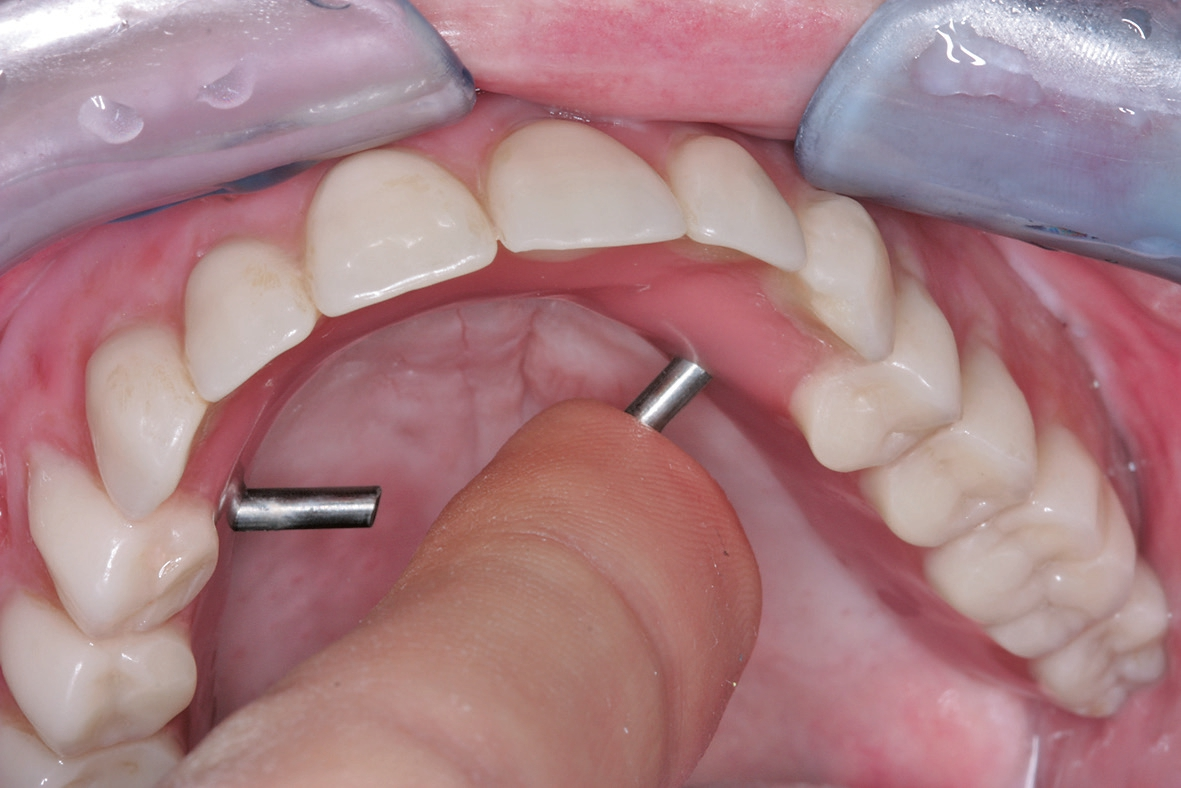

Nach der Einheilzeit wurden die Repositions-Übertragungsaufbauten angebracht und die Implantate konnten im Sinne einer Primärabformung mittels eines konfektionierten Löffels geschlossen abgeformt werden (Abb. 12). Darüber hinaus wurde eine Vorbissnahme durchgeführt, sodass basierend auf diesen Unterlagen im Labor die Sekundärabformung als Pick-up-Abformung vorbereitet werden konnte. Hierzu erfolgte die Verbindung der Abformpfosten auf dem ersten Arbeitsmodell mit starrem Kunststoffmaterial (Pattern Resin, GC Germany, Bad Homburg). Der so entstandene Index wurde anschließend wieder zwischen den Implantatpfeilern getrennt. Intraoral wurde dieser Trennspalt erneut durch Pattern Resin verbunden (Abb. 13), sodass eine hohe Präzision der Abformung durch die Versteifung zwischen den Implantatpfeilern sichergestellt werden konnte.

Dr. Zastrow